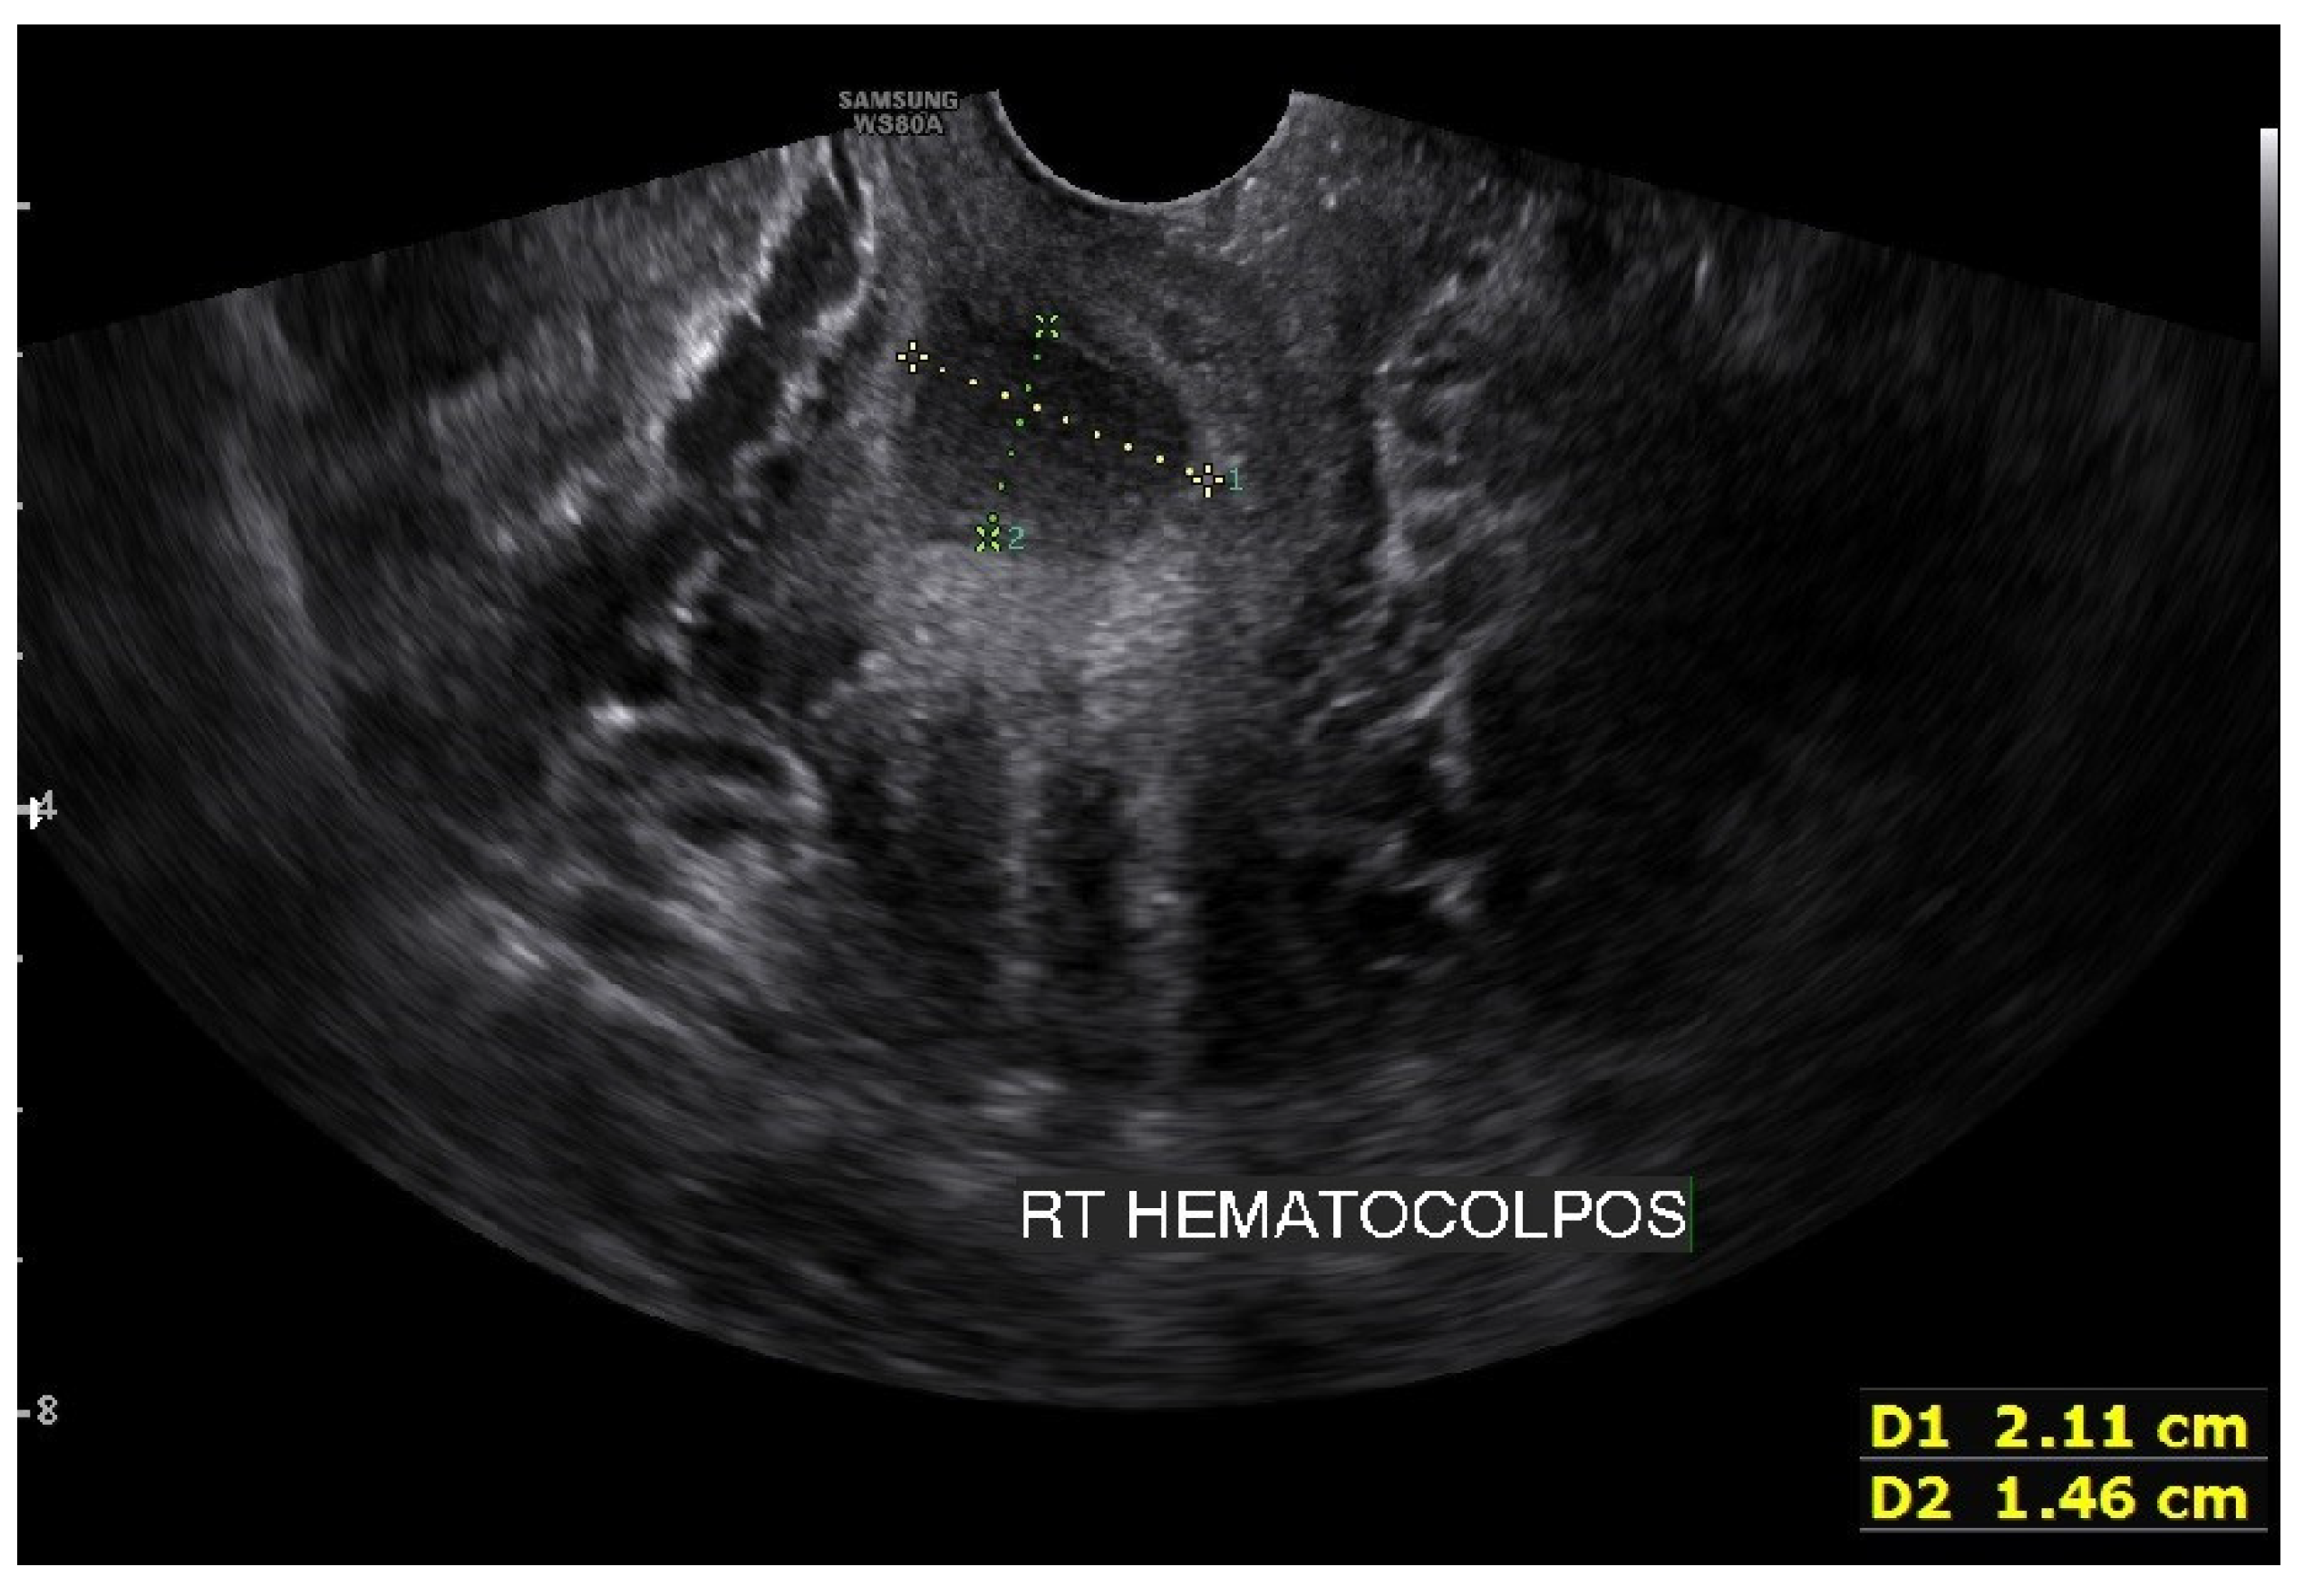

On the abdominopelvic CT image taken at the ER, we noticed she had HWW syndrome (right side hemi-vagina and right kidney agenesis) with acute pyelonephritis (APN) of the left kkidne (Figure 3a,b). After admission, transvaginal USG (Figure 4) and pelvic MRI (Figure 5a–c) were performed. We planned to perform the vaginal wall resection surgery on the next menstrual period as she needed antibiotics treatment for the APN, and the amount of hematocolpos was not so extensive that we could not clearly identify the bulging vaginal wall.

Figure 4.

Transvaginal ultrasonogram image showing approximately 21 mm × 15 mm of fluid collection in the right side obstructed hemivagina. This suggested hematocolpos on the right side was too small and made it difficult to operate on the first visit.